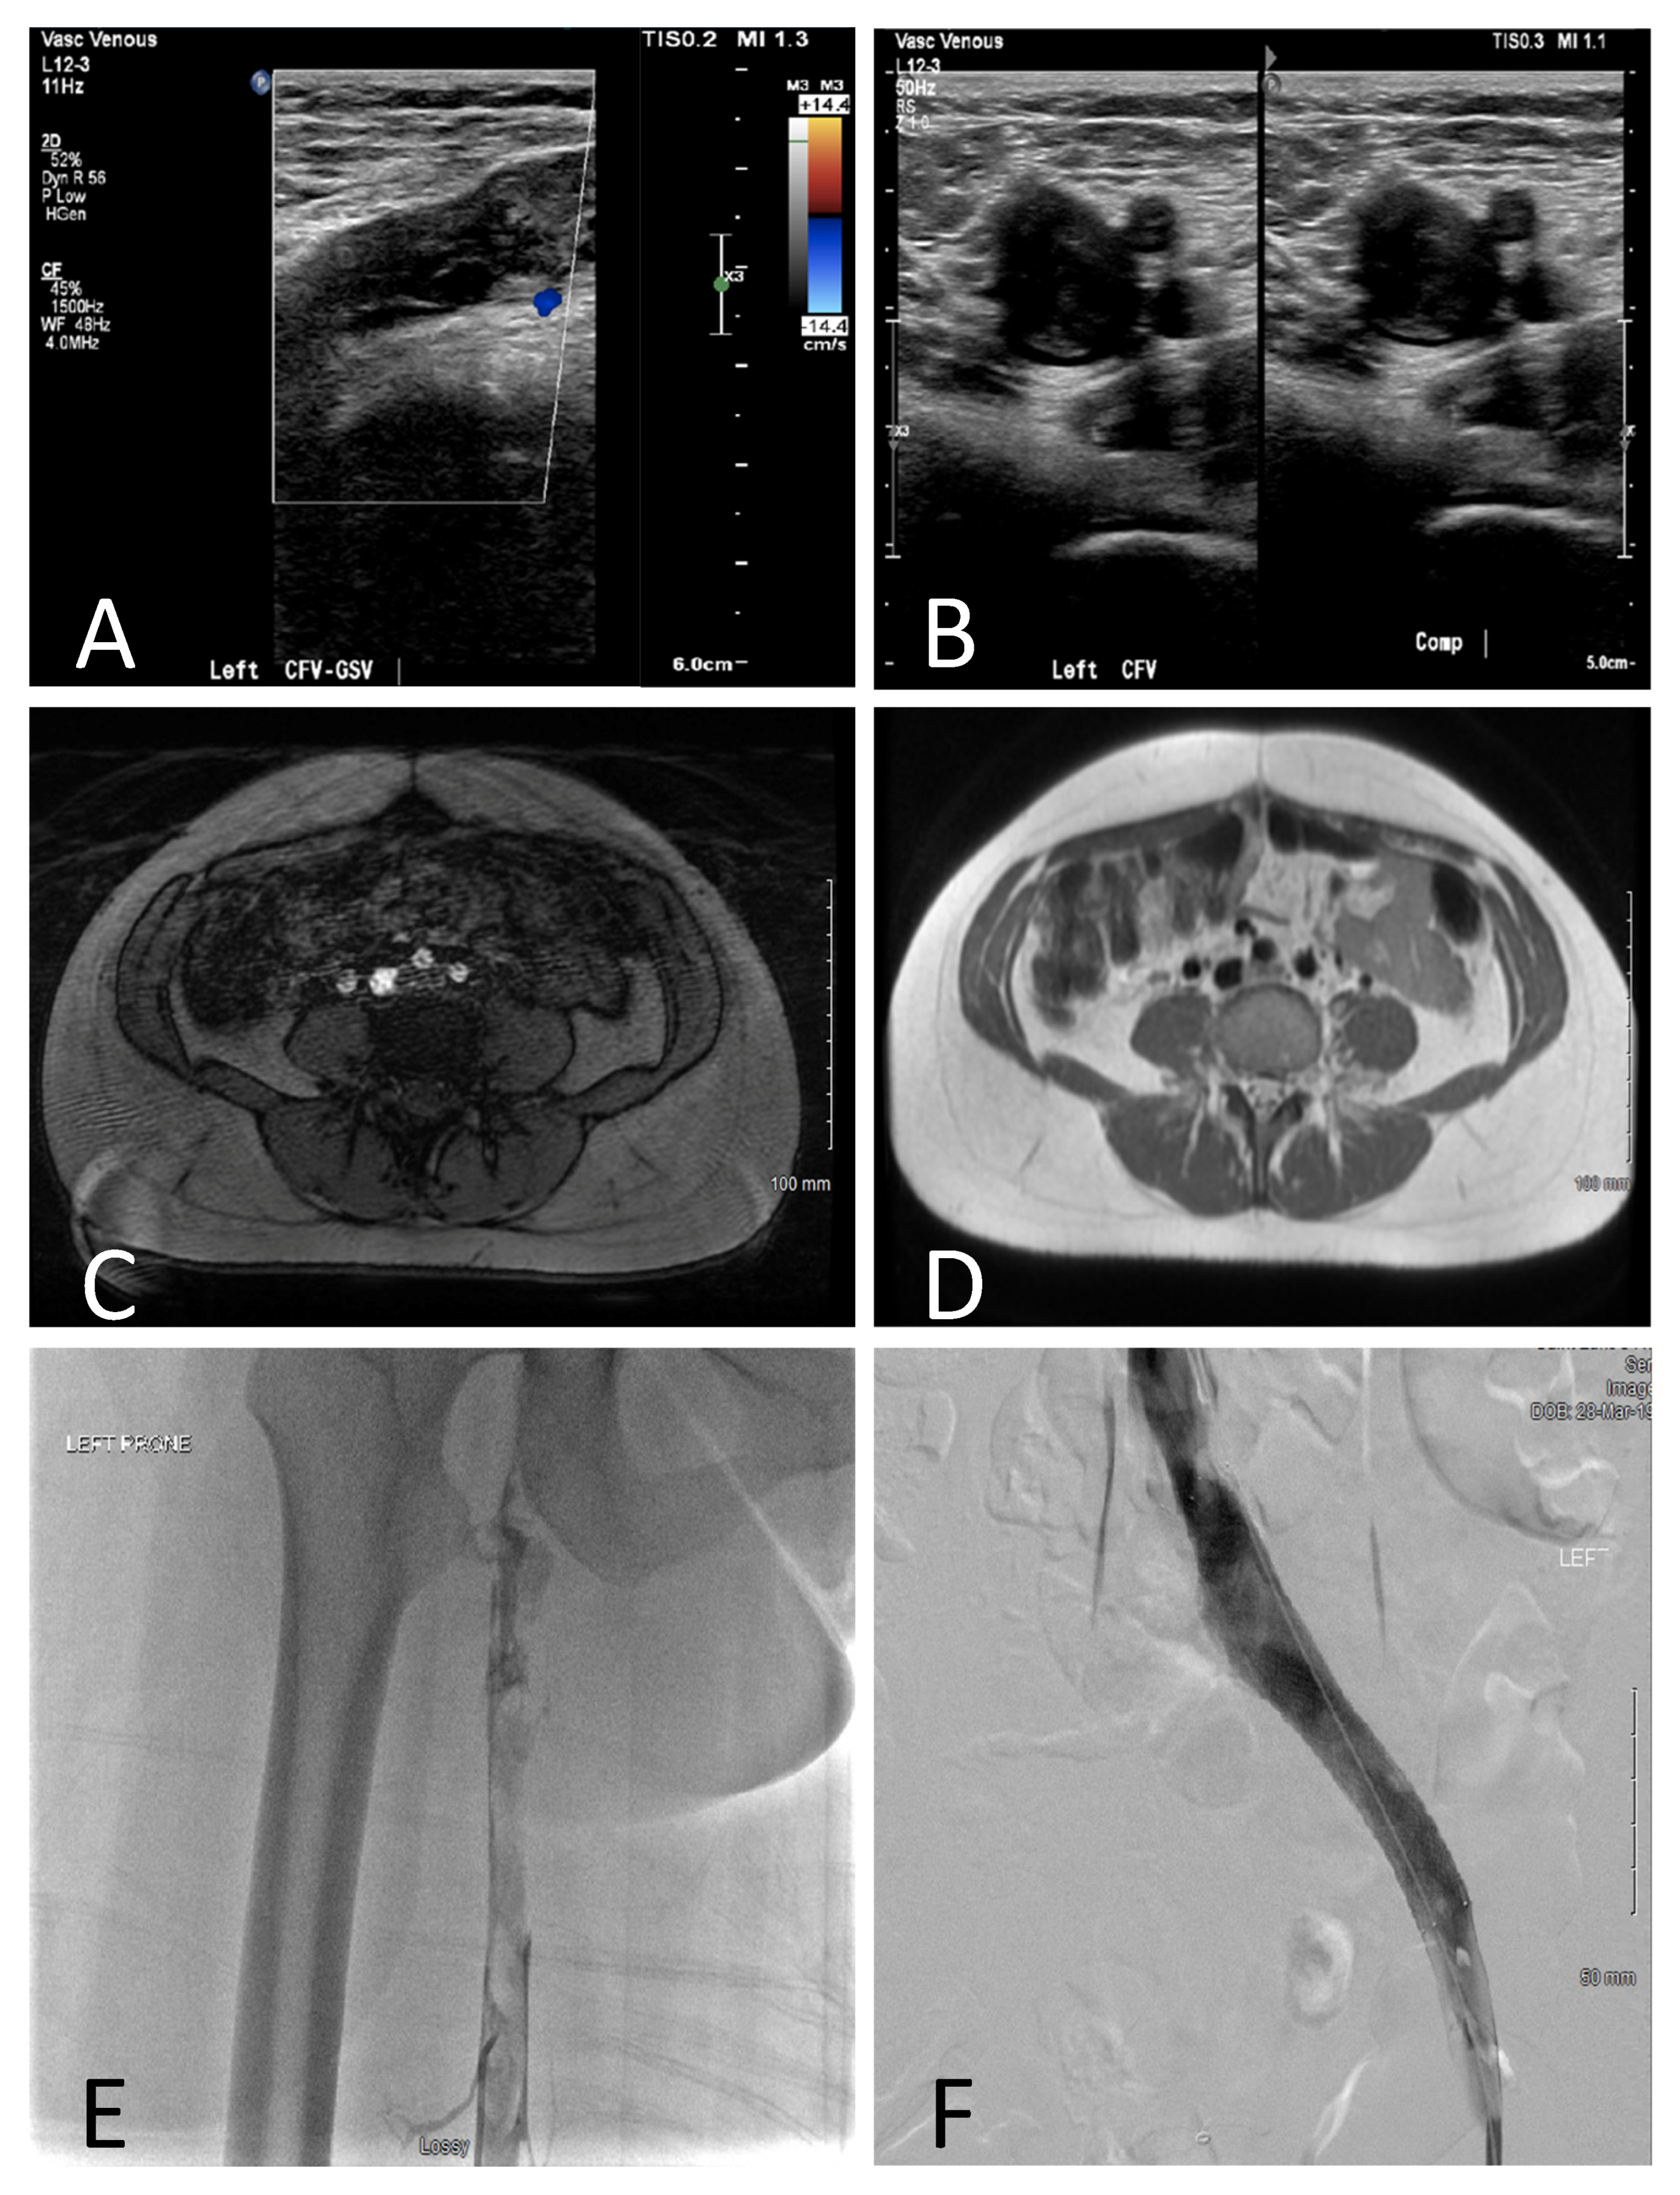

| 1/29 | G2P2 | 9 | Doppler/Duplex US (DVT LCFV to tibial), MRI/A/V (DVT extending from IVC, LCIV, LCFV, c/w MTS), venography (MTS) | UFH, CDT, balloon angioplasty of LCIV and LSFV. Adjusted dose LMWH, continued through 8 wks PP, ASA, compression stockings. LCIV stent PP. | SVD at term | None | |